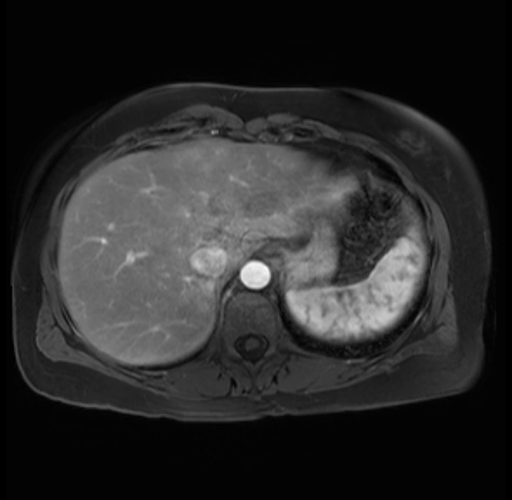

Imaging Analysis

Look through the patient's CT scan to identify any areas of concern for the necessary procedure.

Based on your CT findings, which issue(s) are present and would give reason for "planned slowing down moment(s)" in this case?

Considering a standard distal pancreatectomy procedure, what step(s) of the operation would you do differently in this case?